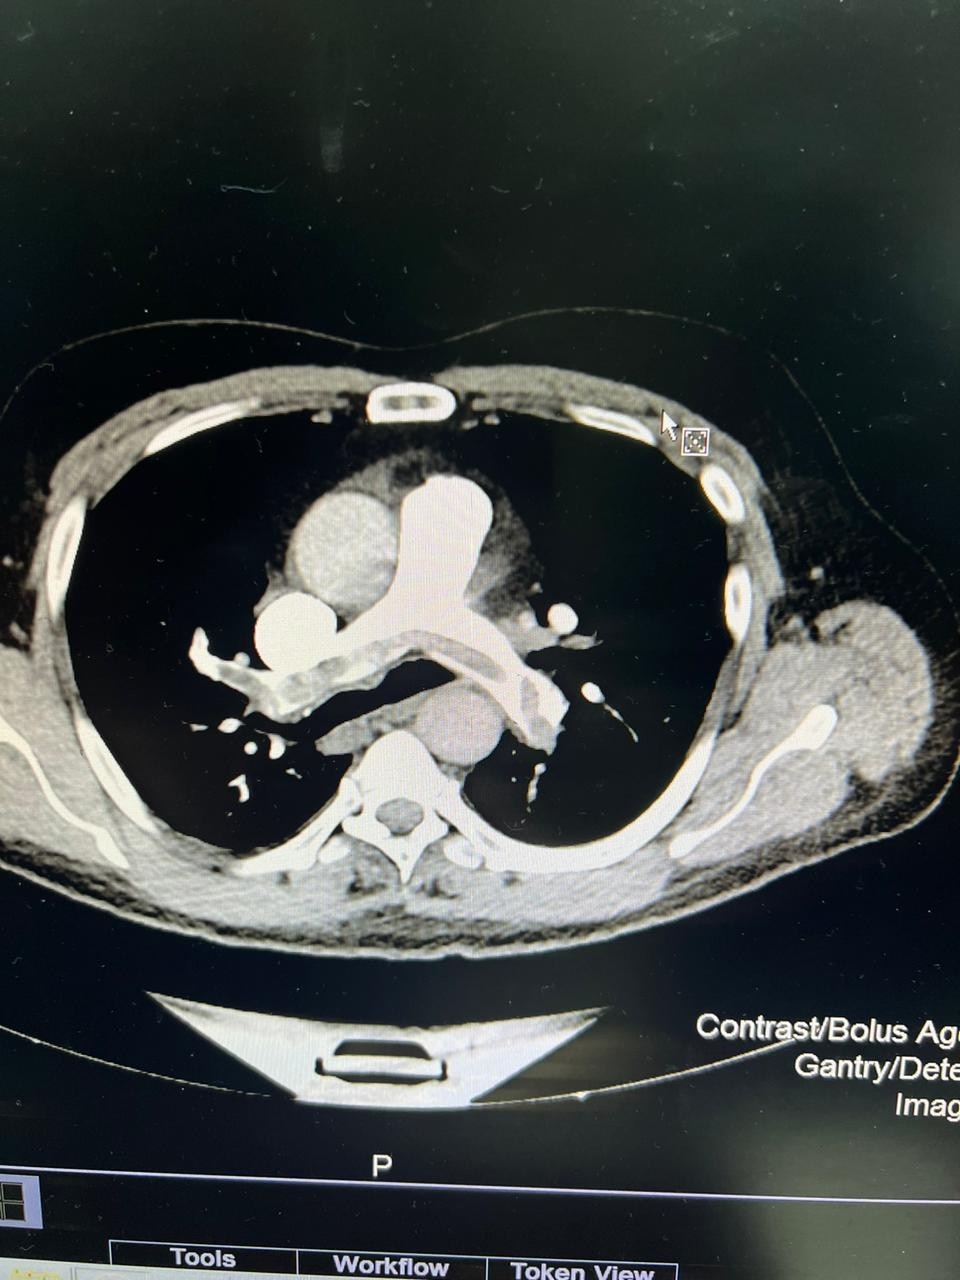

इस तकनीक की मदद से 62 साल के नरेंद्र सिंह का सबसे पहले इलाज किया गया. नरेंद्र सिंह के बाएं पैर में खून के क्लॉट (थक्के) थे, जो उनके फेफड़े तक पहुंच गए थे.

एआई की मदद से इस ऑपरेशन को करने वाले डॉ. तरुण ग्रोवर बताते हैं कि जब मरीज इमरजेंसी रूम में आए, वे सही तरह से सांस नहीं ले पा रहे थे. उनके पैर में दर्द हो रहा था और उसमें सूजन थी. हमने इस तकनीक की मदद से ब्लड क्लॉट को हटाया. इससे मरीज को तुरंत आराम मिला और उनकी सूजन भी कम हुई. मरीज को 48 घंटे के भीतर डिस्चार्ज भी कर दिया गया.